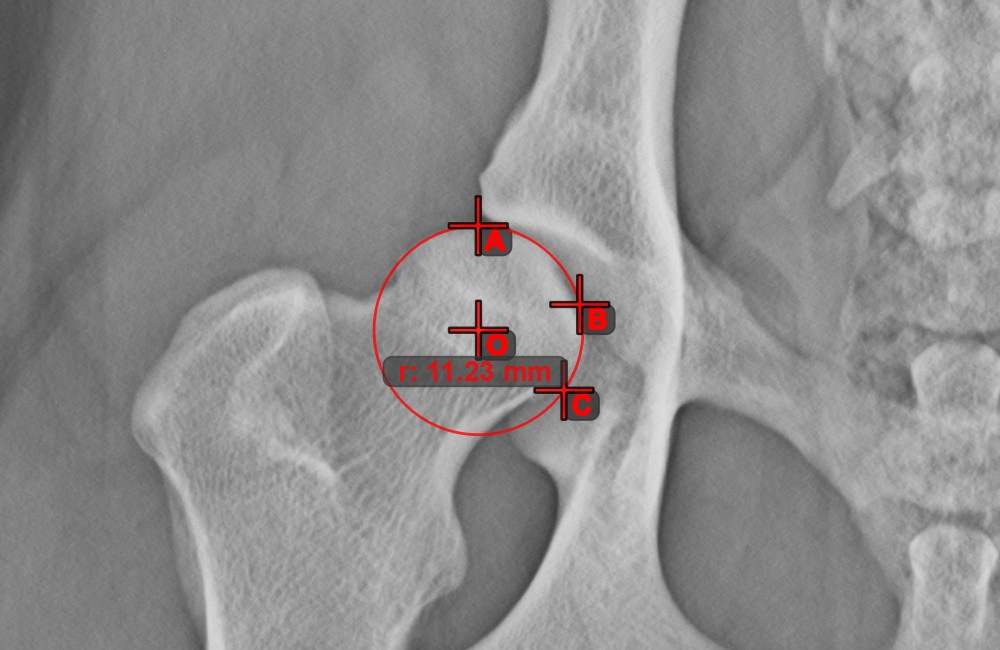

Circle from 3 Points¶

The Circle from 3 Points tool is a simple and effective way to create a circle from just three points.

Start by selecting the tool from the left toolbar and assign it to one of the available mouse buttons. Place the three points of the circle, or select the points from ones available on the scene. The circle will be automatically created based on the position of the three points. The origo of the circle will always be marked with O. The radius of the circle is automatically calculated.

Modify the position of the three points to change the radius of the circle by using the Select/Move Item tool.